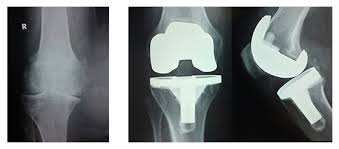

The company ORTHOPEDIC NIKIFOROV was founded in 1998 by the candidate of medical sciences. doctor of orthopedic-traumatologist of the highest category Nikiforov IA Owing to high professionalism and results of work, ORTONIC has gained well-deserved reputation and reputation among colleagues and population of Dnepropetrovsk region and CIS countries (Russia, Moldova, Armenia, etc.). The principle of the enterprise is NO IMPOSSIBLE, it is based on knowledge, experience and active implementation of modern technologies in orthopedics and traumatology. Conservative methods of treatment include individual selection of medicines, therapeutic blockades, manual therapy, massage, physiotherapy (vibration table, magnetotherapy, bioptron, electromyostimulation, etc.), rehabilitation with the suggestion of the necessary concomitant devices and means for the fastest recovery (corsets, bandages, various joint fixators, crutches, walking sticks, etc.). Various minor invasive interventions (chymonucleolysis, vertebroplasty, kyphoplasty, percutaneous nucleoplasty using cold plasma) that are performed on an outpatient basis are successfully used to treat problems associated with spine pathology. The latest modern treatment methods introduced in our company are endoscopic operations using the TYSSES technique of Joimax (Germany) with intervertebral hernias, stenosis and other pathologies of the spine, which allow to avoid complications occurring during open operations and the accompanying general anesthesia. We have many years of successful experience in traditional and modern minimally invasive endoprosthetics of large and small joints, which remains the main direction of our activity. Our company is the exclusive representative of the German company IO International Orthopaedics Holding GmbH, which based on the already known prostheses, its ideas and technological capabilities, has developed and implemented a new concept in hip replacement - an artificial joint prosthesis (ICON). We assist interested colleagues in training the operative technique for installing an artificial joint prosthesis - ICON, both in the workplace and in Germany. For 20 years we have been successfully cooperating with Sanitatshaus Gerd Klinz ortho team, an enterprise that for 20 years has been one of the leading places in Germany for the production of functional prostheses of the upper and lower limbs, as well as cosmetic prostheses of limbs and other body parts (nose, ears, eyeballs, fingers). We have an atmosphere of friendliness and human participation. Politeness, benevolence, the desire to understand and help is the basis of our attitude towards patients. We are always glad to see you and will do our best to make you feel great! We are waiting for you at: Ukraine, Dnepr, Gagarin Ave., 13 (under reconstruction) on all questions to address: tel .: +38 (050) 488-88-92 E-mail: orthonik.ukr@gmail.com Germany, Spine Nano Klinik, Zeppelinstr. 21, Potsdam Tel. +4901801121919 E-mail: kmw.nikiforov@hotmail.de